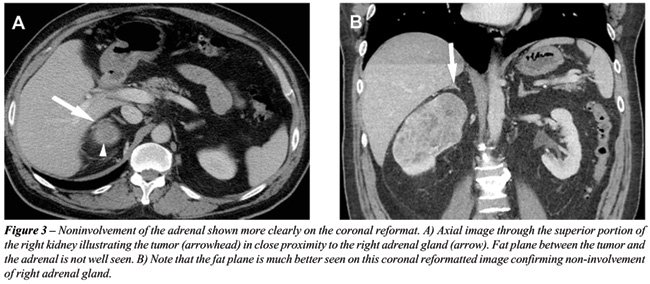

With the rapid acquisition of multiple simultaneous slices and thin-section reformatted coronal and/or sagittal images, the 64-slice CT scanner provides excellent detail in demonstrating local extension to the bowel and retroperitoneum (see Figures-2, 3, 5, 6 and 7). Multiplanar three-dimensional reconstruction techniques including volume rendering, maximum intensity projection and shaded surface display provide comprehensive information about the relationships and possible involvement of vascular structures in renal neoplasms.